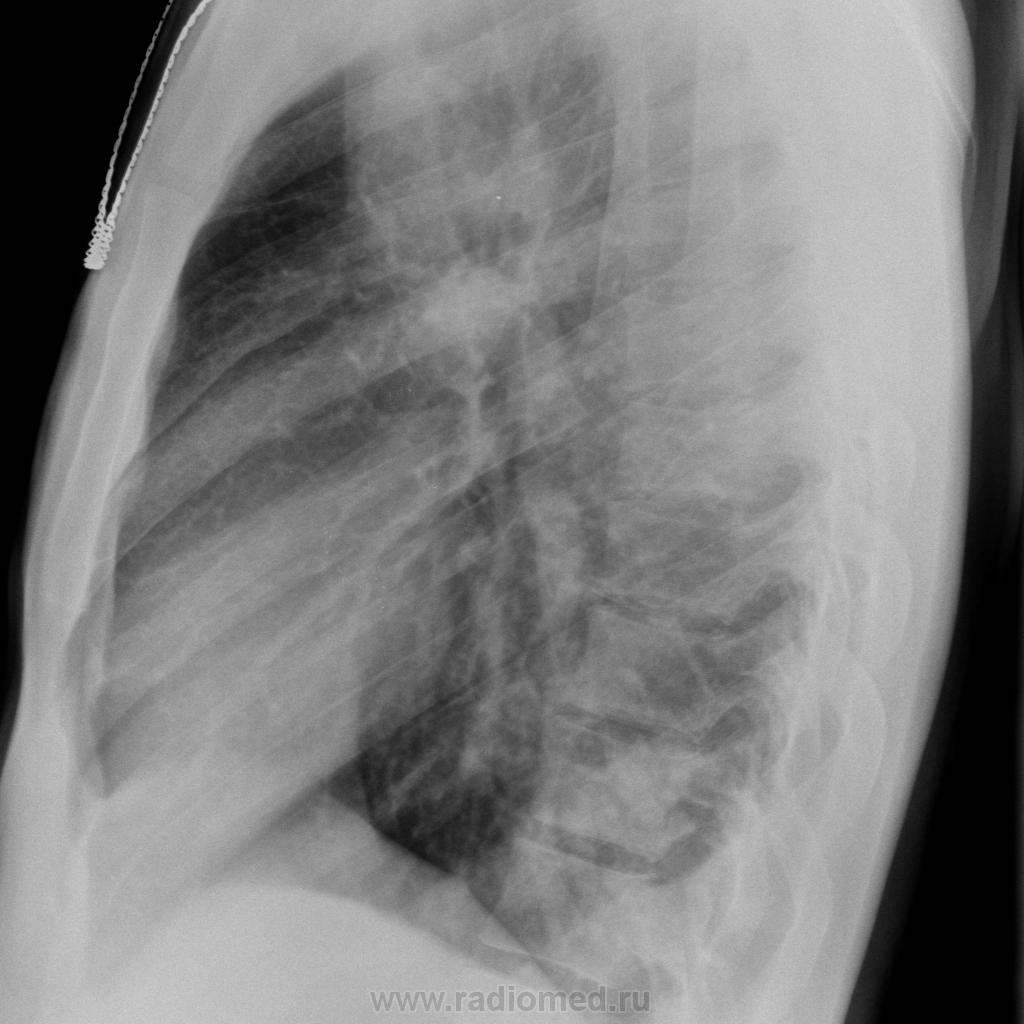

Мужчина, 24 г. Пришел на ФЛГ с жалобами на  кашель со скудной мокротой, повышение температуры до 38,5 С в течение 5 дней

В анамнезе - в 2009 будучи в армии болел TBC, оперирован, удалены S1,2 справа. Сразу оговорюсь - сделать линейные томограммы нет возможности.

Расценила изменения слева как пневмонические, но очень опасаюсь проглядеть tbc.

оперированного по поводу туберкулеза легких, появление бронхолегочных  признаков заставляет всегда думать о рецидиве заболевания. Это правильно. В данном случае имеет место пневмония.  Рекомендуйте исследование мокроты на МБТ №3. После лечения пневмонии представьте на сайт контрольные снимки. С уважением Nikolas

Коллеги, объясните что за тень на фоне позвонка на прицельном снимке?